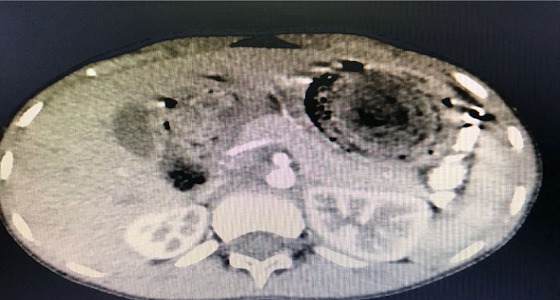

إجراء أول جراحة منظار بالقصيم لاسئصال كتلة محسوسة بمعدة طفل